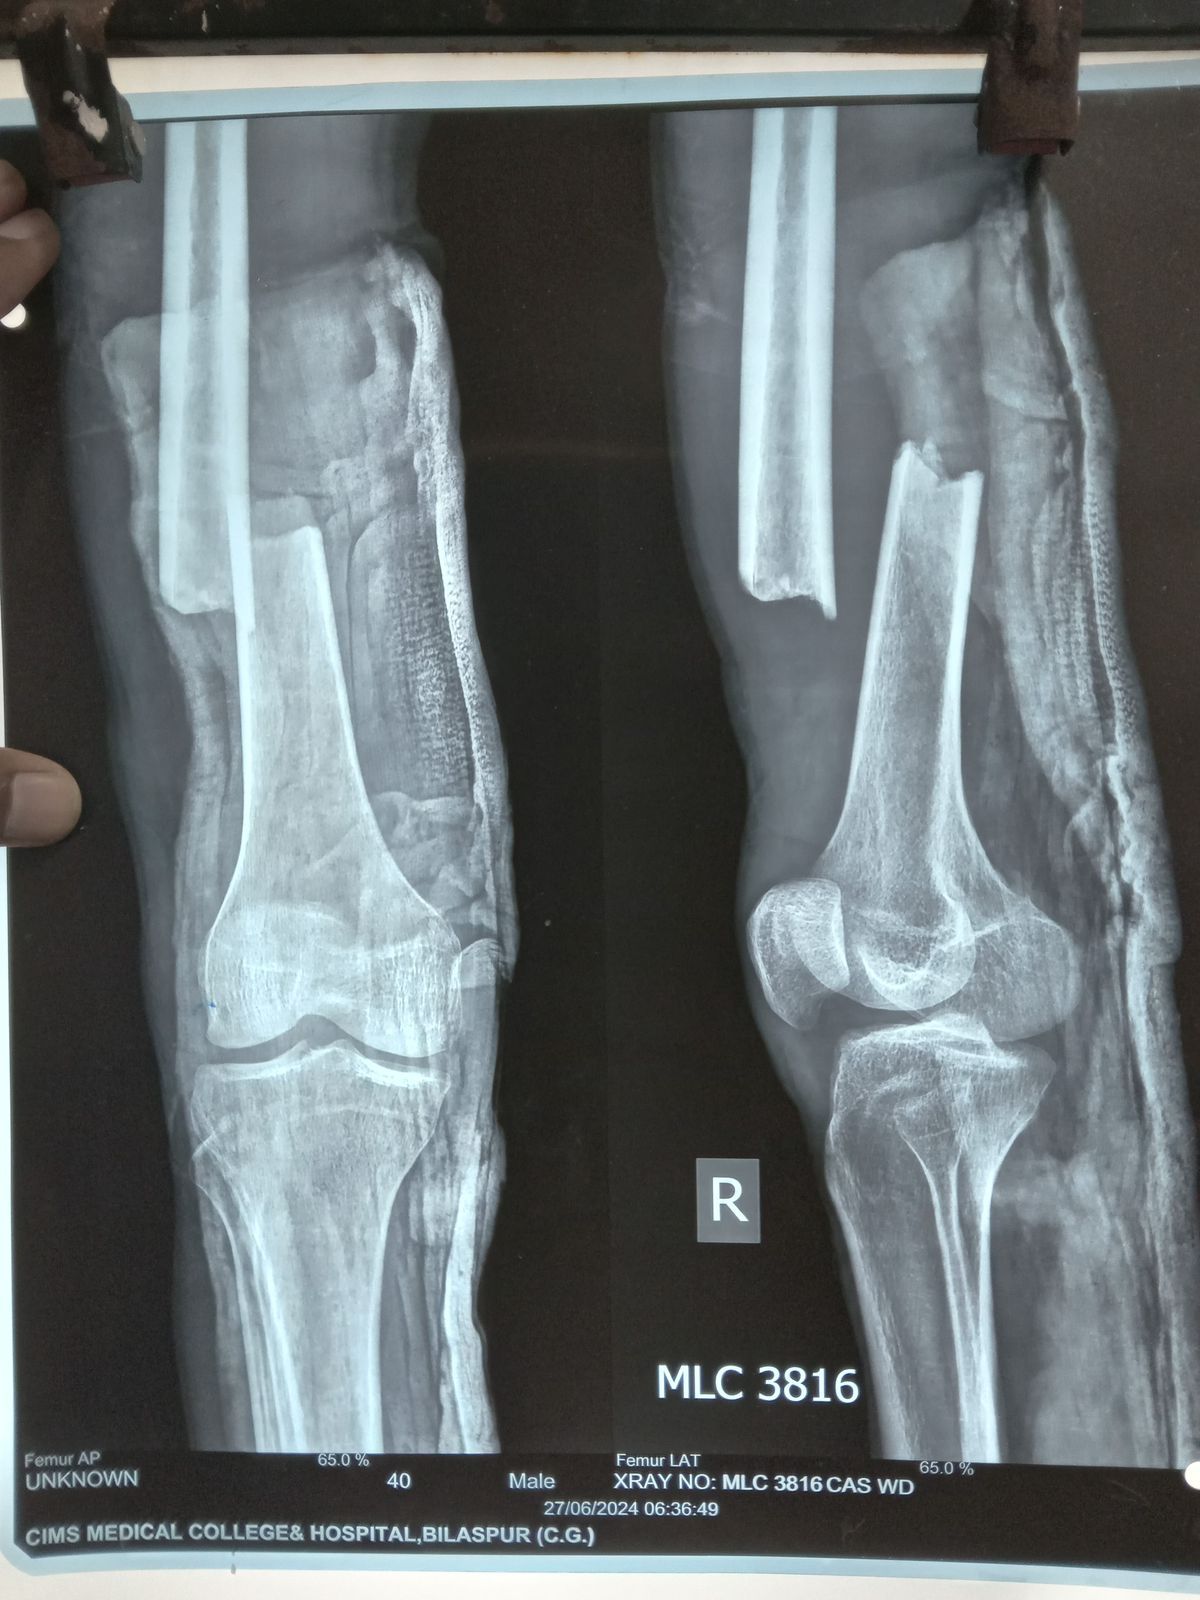

2 अज्ञात उम्र 40 साल जो 24 जून2024 को जिला अस्पताल कबीरधाम से रेफर होकर सिम्स भर्ती कराया गया । जो मरीज लावारिस था पैसों के अभाव में इलाज नहीं हो पा रहा था। सिम्स में इलाज डॉक्टर दीपक जांगड़े ने पूरा इलाज निशुल्क निस्वार्थ भावना से से किया और उनके पूरे टीम ने एनेस्थीसिया डॉक्टरों की टीम डॉ राकेश निगम के मार्गदर्शन में सफल ऑपरेशन हुआ इस पूरे ऑपरेशन पर डॉक्टर को बधाई सिम्स के अधिष्ठाता डॉक्टर के के सहारे ने दी।